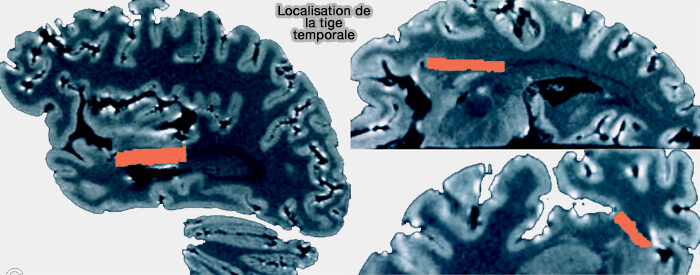

Tige temporale

(Figure : vetopsy.fr d'après Kier et coll)

1. La tige temporale (temporal stem) est constituée de fibres de matière blanche qui traverse un espace du lobe temporal situé à l'intérieur d'une ligne reliant (MR Imaging of the Temporal Stem: Anatomic Dissection Tractography of the Uncinate Fasciculus, Inferior Occipitofrontal Fasciculus, and Meyer’s Loop of the Optic Radiation 2004) :

- le sillon inférieur de l'insula ou péri-insulaire inférieur,

- le limen insulaire,

- la sillon latéral (de Sylvius), au niveau de l'amygdale,

- la queue du noyau caudé.

Vous pouvez lire : A Understanding of the Temporal Stem (2010) qui décrit complètement cette structure anatomique complexe.

2. Les fibres qui composent la tige temporale sont :

- la capsule extrême,

- le faisceau unciné,

- le faisceau fronto-occipital inférieur,

- la commissure antérieure,

- l'anse pedunculaire,

- le pédoncule thalamique inférieur avec les radiations optiques.

Ces fibres communiquent avec le lobe frontal, les corps striés, le thalamus, l'hypothalamus, le lobe temporal controlatéral et la région septale à travers la tige temporale.

(Figure : vetopsy.fr d'après Choi et coll)